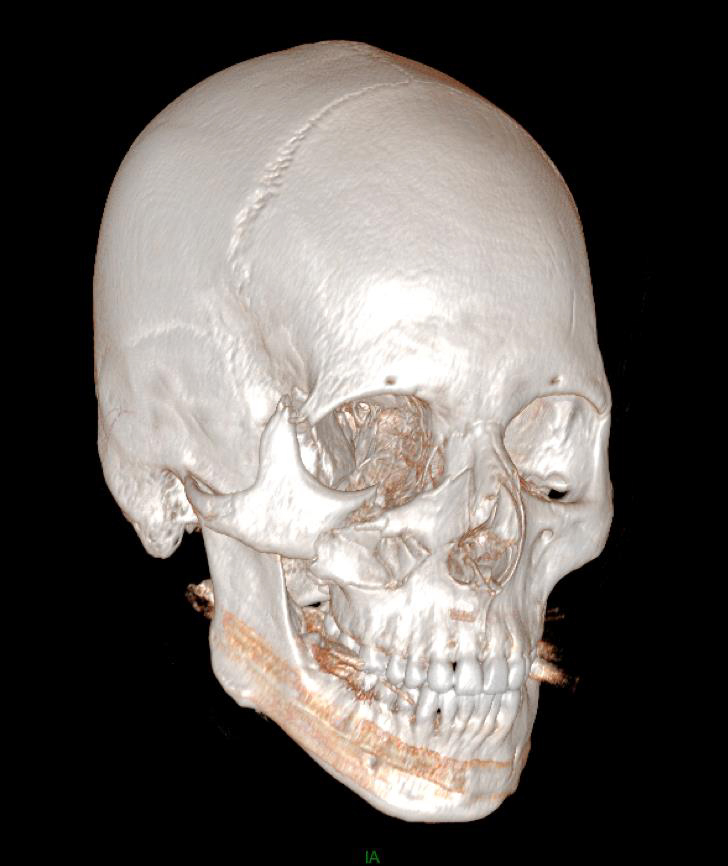

De garde, vous êtes appelé en salle de surveillance post-interventionnelle (SSPI) dans votre hôpital où vient d'être admis un patient conduit sur place par le service d'aide médicale d'urgence (Samu). Il s’agit d’un jeune homme de 20 ans, Monsieur D. Il aurait été victime, entre autres, d’un tir de Flash-Ball lors d’une rixe. Le projectile l’a atteint au niveau de la pommette et de l’orbite droites. Il présente une plaie de la région jugale haute, un œdème des paupières supérieure et inférieure. Vous ne visualisez pas le globe oculaire spontanément. Il est hémodynamiquement stable.

Traumatisme orbitaire = à risque de fracture des parois de l’orbite et donc d’incarcération d’un muscle oculomoteur.